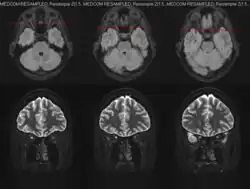

MRT bei einer rechtseitigen Neuritis nervi optici

Augenärztliche Untersuchungen sind häufig ohne pathologischen Befund, der Augenhintergrund erscheint bei der Ophthalmoskopie unauffällig („der (Augen-)Arzt sieht nichts und der Patient sieht nichts“). Nur wenn die Entzündungsherde nahe am Auge liegen, kommt es zu einer Papillenschwellung, die aber auch bei ganz anderen Erkrankungen (Hirndruck) auftreten kann. In der Spätphase nach Abheilen der akuten Entzündung kann eine auffällige Blässe meist im temporalen (schläfenseitigen) Teil der Papille verbleiben. Die Diagnose einer demyelinisierenden Erkrankung des Sehnervs lässt sich am besten mit Hilfe der Optical Coherence Tomography (OCT), spezifischer Antikörper im Blut und einer kontrastmittelunterstützten Magnetresonanztomographie (MRT), welche die Orbita beinhaltet, stellen und es zeigen sich meist verminderte Nervenleitgeschwindigkeiten bei der Untersuchung der visuell evozierten Potentiale.[1]